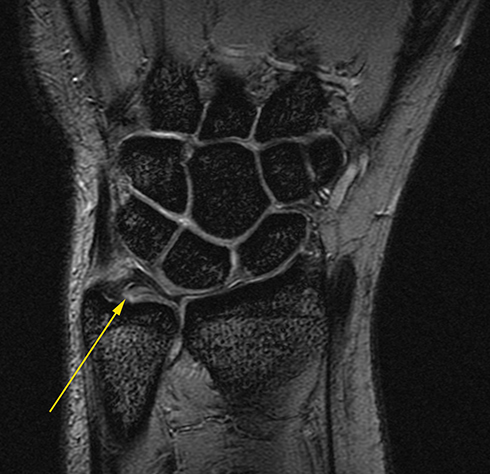

Scapholunate Tear

We acquire many different types of images and compare them to find subtle abnrmalities. In this case there is damage to the ligament that joins the scaphoid and lunate bones of the wrist (yellow arrow).